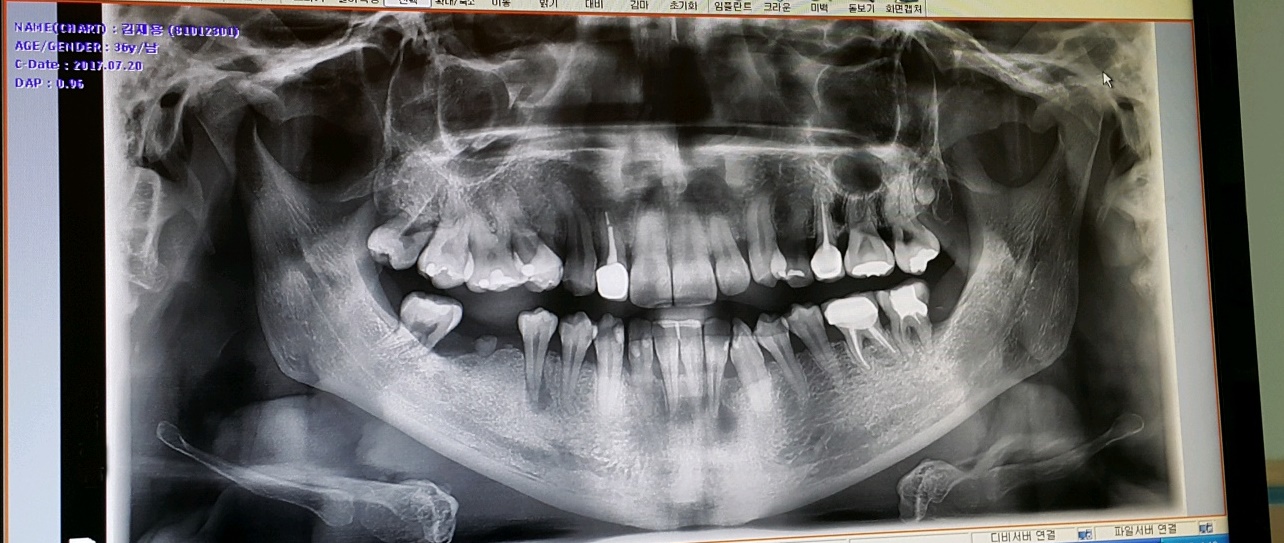

3년6개월에 거쳐 모든 과정이 끝난 지금의 내 치아상태인데

상악은 확실히 바뀐게 보이긴 한다..

그런데 밑의 앞쪽 치아들 중 한 치아는 강제로 이동되서 약간 비스듬히 뿌리가 잡혀있는게 보인다.

아마도 유지장치가 없다면 이 치아가 다시 원래자리로 돌아가겠지...